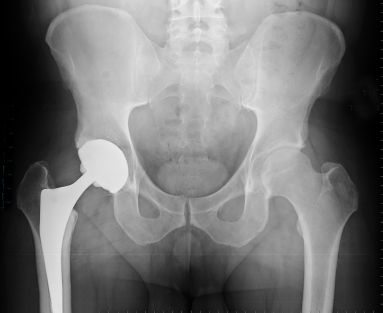

Hip replacement surgery while common, is risky and many people never walk the same as they did with their original joint.  Improving the function of a hip joint that is tight and becoming arthritic can prevent the need of joint replacement if performed regularly enough by a therapist and the patient.